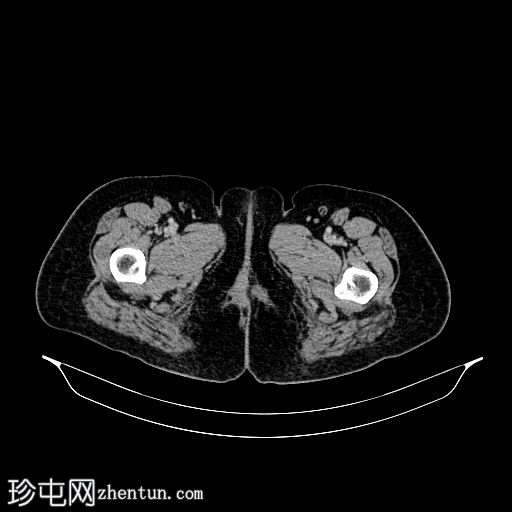

CT

轴位增强扫描(C+)门静脉期

移位的宫内节育器(IUD)长臂两次穿透增厚的膀胱前壁。中部位于膀胱内,周围有结石和气体。